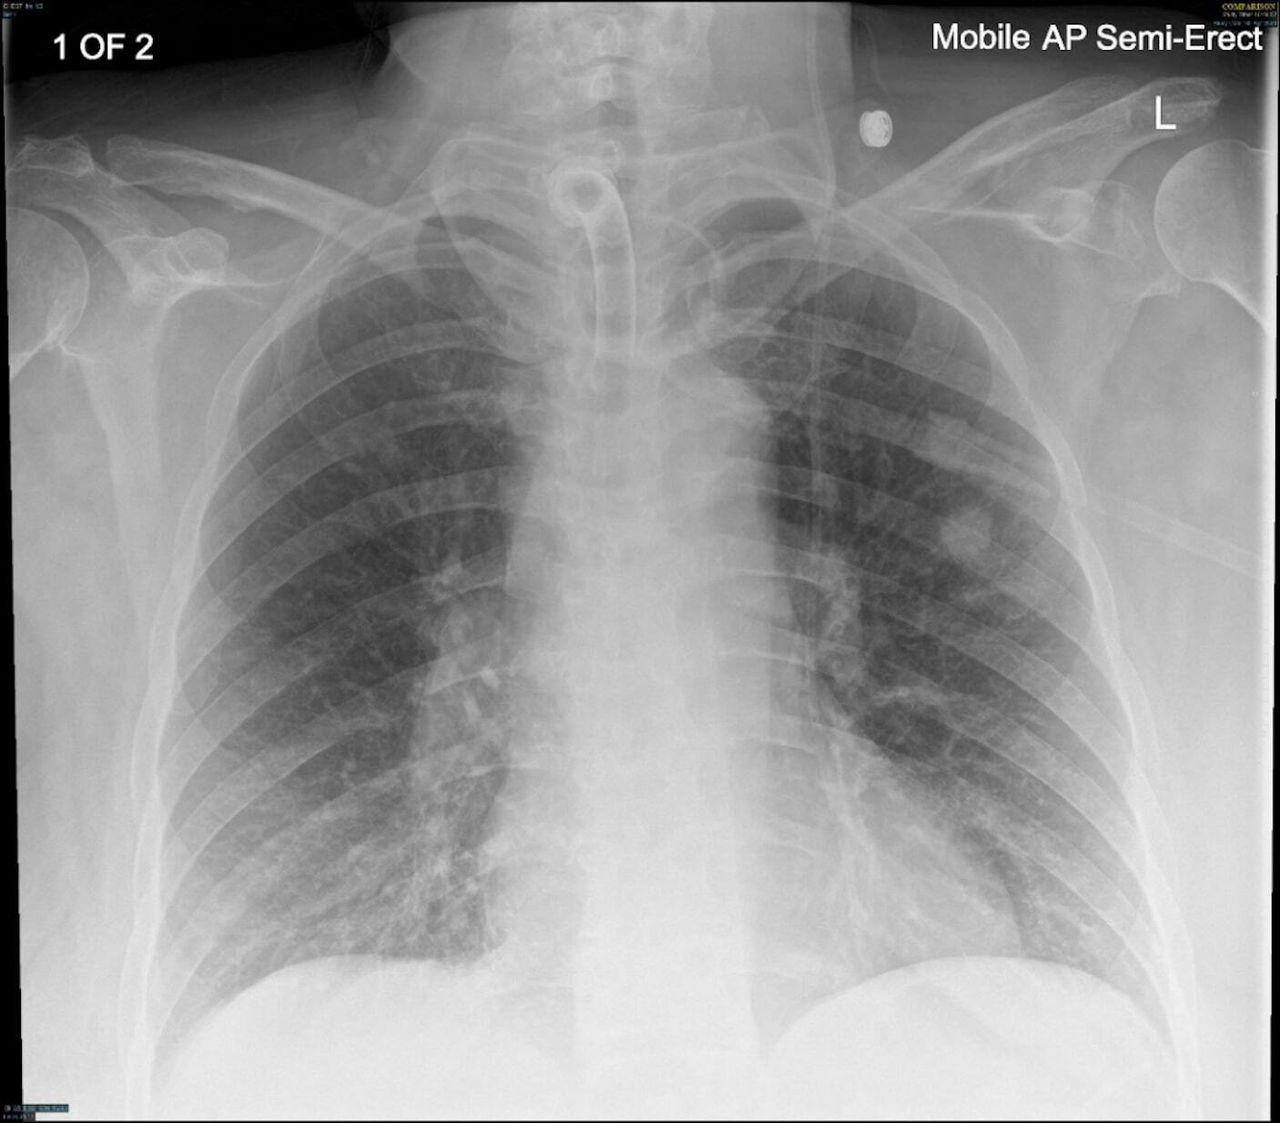

Pour localiser le morceau d’écouvillon, un scanner a été pratiqué qui, au départ, n’a rien montré d’anormal. Un nouveau scanner a ensuite mis en évidence des signes d’inflammation dans un poumon, ainsi qu’un rétrécissement des voies respiratoires.

Une endoscopie a été nécessaire pour retirer l’objet, qui s’était logé dans la bronche lobaire, la première subdivision des bronches principales à l'intérieur des poumons. L’écouvillon a été retiré avec succès.